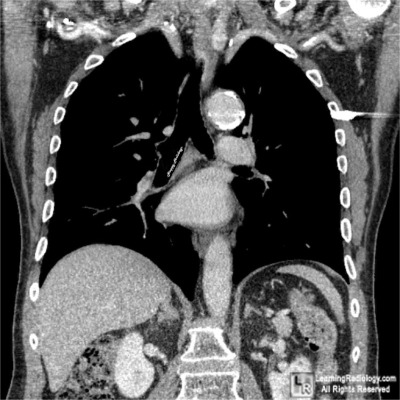

Coronal Reformatted CT Scan of the Chest

This is a retouched photograph of a coronal reformatted CT scan of the chest. There is no foreign body present.